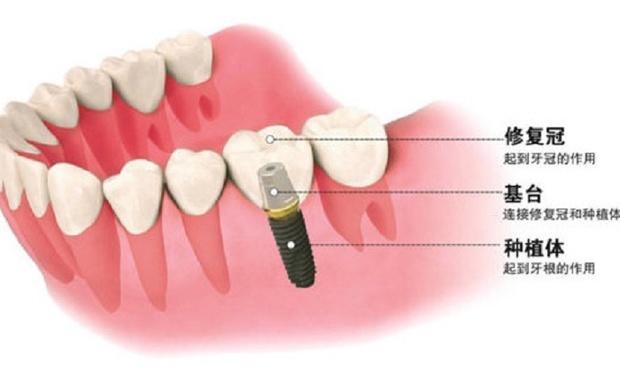

3. 植入種植體:這個(gè)時(shí)候開始進(jìn)行第一期手術(shù),手術(shù)將在牙槽骨上選擇合適的位置打洞,植入種植體后縫合創(chuàng)口,正常情況下整場(chǎng)手術(shù)時(shí)長在半個(gè)小時(shí)左右。

6. 安裝基臺(tái):骨愈合后就可以進(jìn)行二期手術(shù)使種植體穿出牙齦,為了幫助牙齦軟組織更快的愈合,會(huì)通過手術(shù)把種植體的覆蓋螺釘取替換成愈合螺釘。

7. 覆蓋義齒:兩至三周待軟組織成型后,就可以把愈合基臺(tái)換成基臺(tái)佩戴種植牙冠了;至此種植牙全部流程都已全部完成。